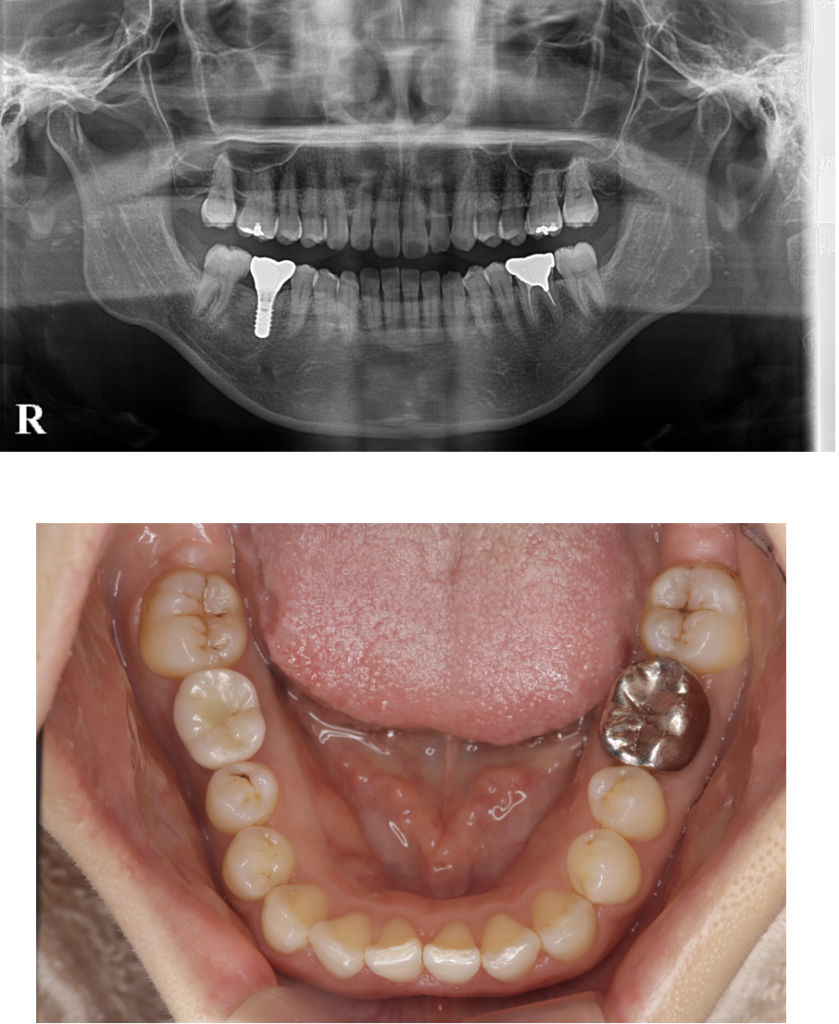

インプラント 1 No.1

Before

After

| 治療方法 | インプラント 歯を失った顎の骨に、体に馴染み易いチタン材料で作られた人工歯根を埋め込みます。それを土台にセラミックで作った人工歯を取り付ける治療法です。 |

| 治療のデメリット | ・神経や血管を傷つける可能性があるので、当院ではCT撮影を行って診断をし、さらにコンピューターシュミレーションを行い神経や血管の立体的な位置を把握してインプラントを安全な位置に埋入します。 ・上顎は上顎洞という空洞があり、そこを削ってしますと炎症が起きてしまうため、CT撮影でしっかり診断をしてから、さらにコンピューターシュミレーションを行い、手術を行います。 |

| 費用 | ¥460,000円×2本=¥920,000 |

| 通院回数 | 3ヶ月〜9ヶ月 |

| 備考 | 院長より 残すことが難しい状況になった歯を抜いて、インプラントを2本埋入しました。 骨もしっかりとあり良い状況です。まだまだこれから長い間使って頂けると思います。 |